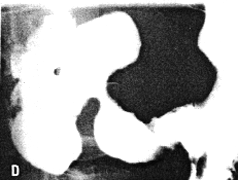

Case 33.10 S.F., 49 year old male. Radiology: 6.0 cm nodular and constricting pyloric filling defect. Smooth, concave indentation base of duodenal bulb (Fig. 33.10). Operation: Pyloric mass with serosal spread, adherent to pancreas. Lymph node metastases. Billroth II. Gastric histology: well differentiated adenocarcinoma. Duodenal histology: spread into serosa and muscularis of duodenum. Duodenal mucosa and Brunner's glands free of tumor cells.

![]() |

| Fig. 33.10.Case S.F. Nodular and constricting pyloric filling defect. Smooth, concave indentation base of duodenal bulb. |